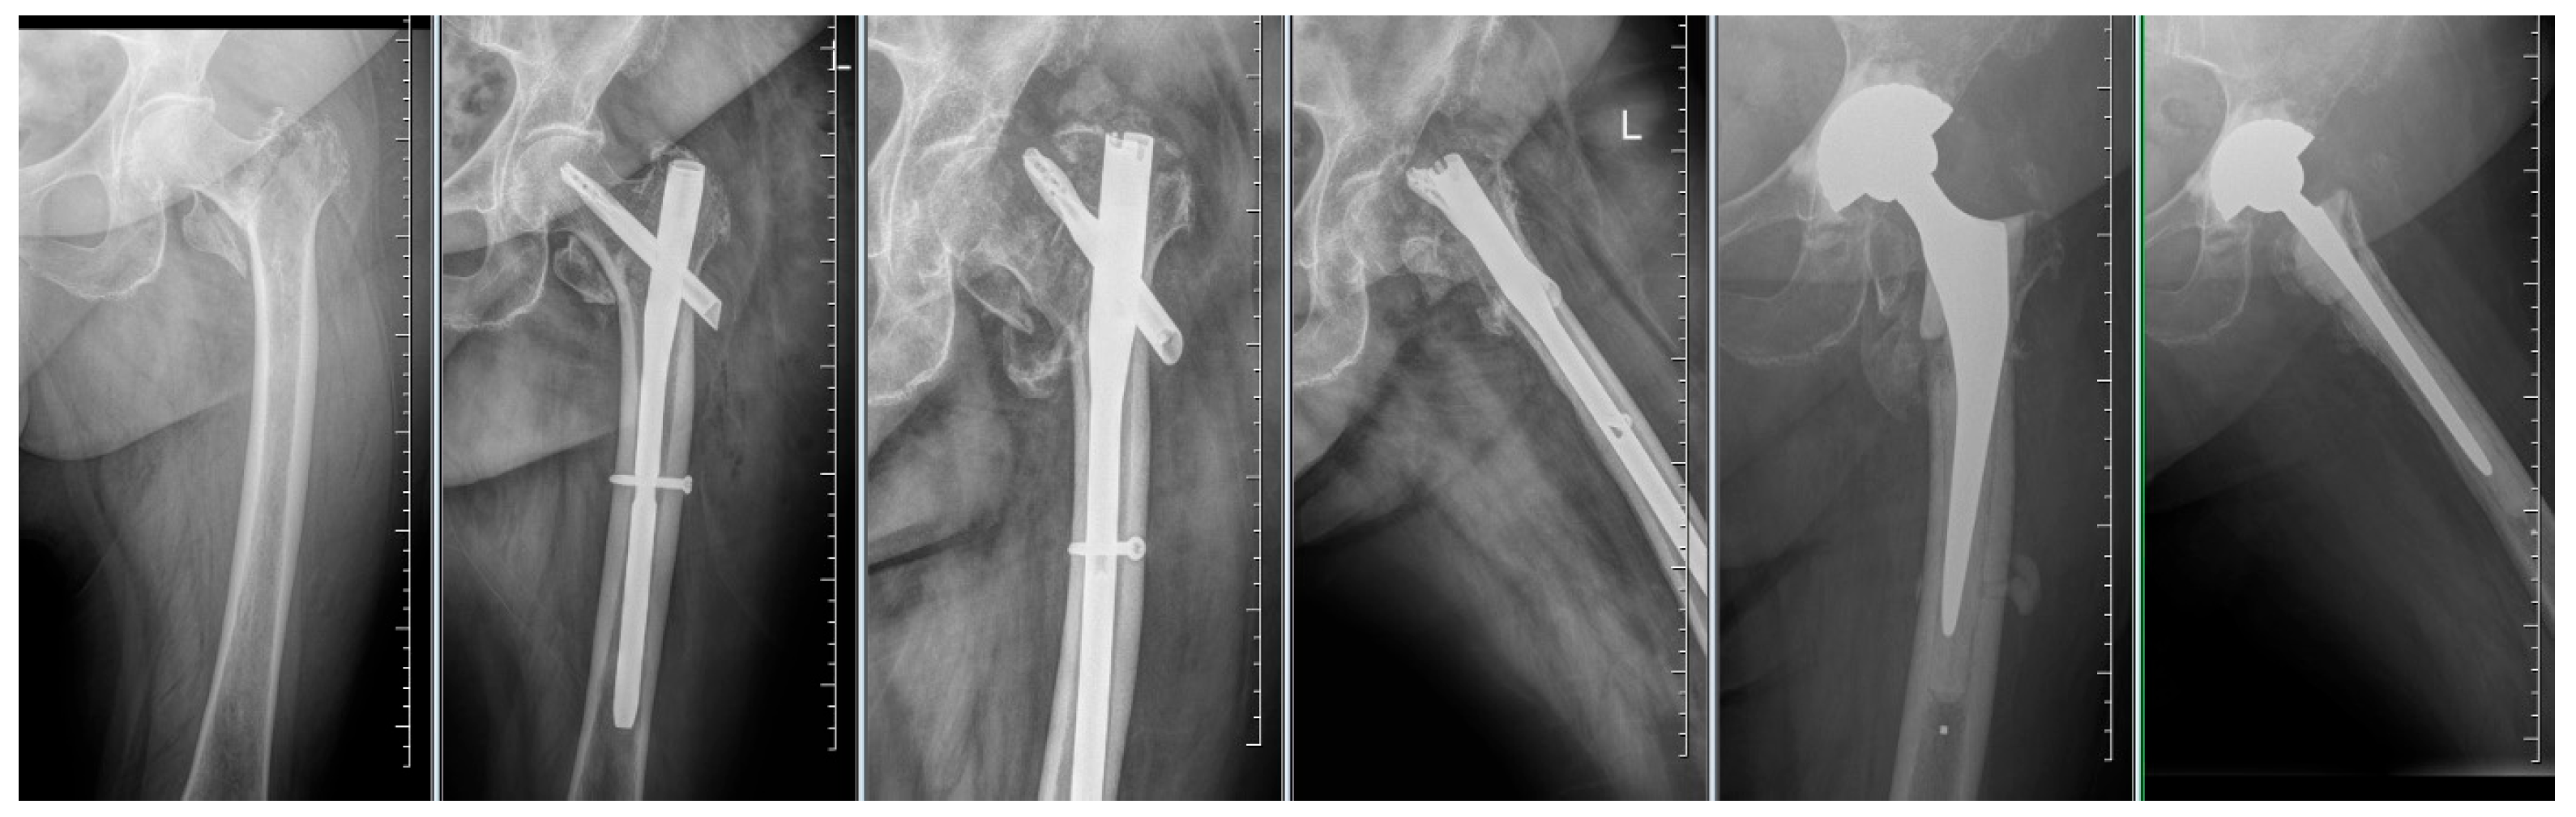

Figure 5.

Failure of osteosynthesis and cut-out of the blade after osteosynthesis using TFNA. Extraction of TFNA and implantation of a total hip endoprosthesis.

By evaluating the X-ray parameters, eight patients in the cohort in whom postoperative varus deformities of the femoral neck were greater than 10° were founded. Four patients did not have cement augmentation and four had cement augmentation of the nail. In three cases, the blade cut-out and, thus, failure of osteosynthesis was identified. In two women and one man with blade cut-out, a TFN-A implant without cement augmentation was implanted (Figure 3, Figure 4 and Figure 5). In these three cases, the medial cortical line and anterior cortical line were repositioned within 3 mm of dislocation at the anatomical interface. The blade cut-out in the group with cement augmentation was not observed.